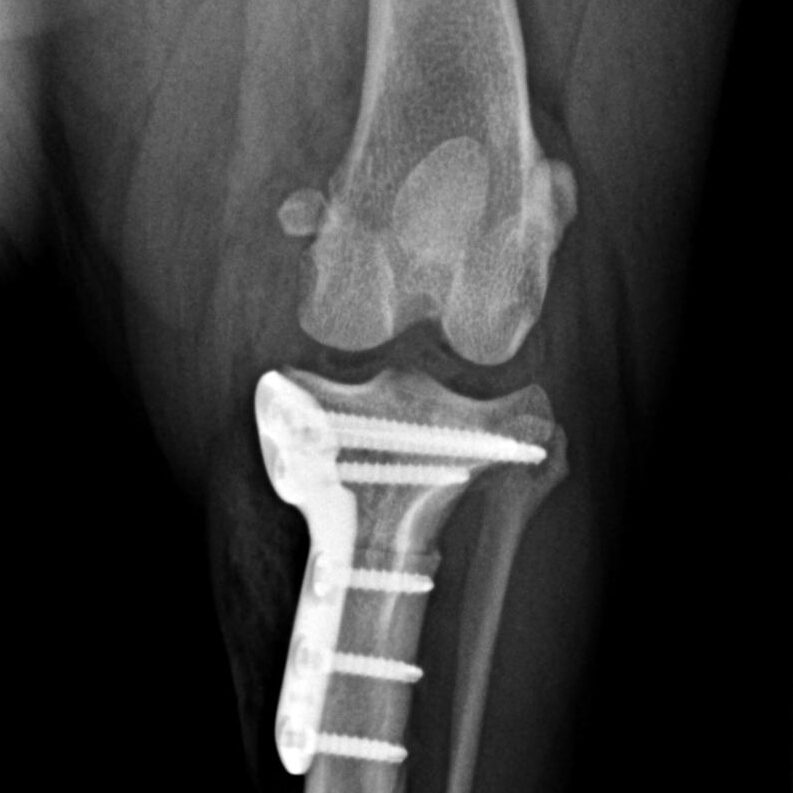

Knochenchirurgie

- Frakturversorgung, Korrekturosteotomie, u.a., verschiedenste Methoden wie Fixateur externe, interne Implantationen von Drähten, Nägeln, Schrauben, Platten inklusive SOP u.a.

Gelenkchirurgie inklusive Arthroskopie

- Kreuzbandriss, Meniskusläsionen, Patellaluxation, laxe Schulter, Isolierter Processus anconaeus, Fragmentierter Processus coronoideus, Osteochondrosis dissecans, Luxationen, Frakturen u.a.